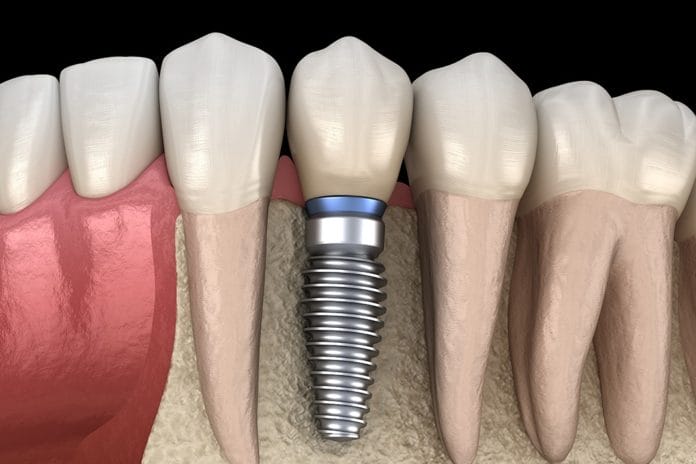

How to Recognize the Most Common Complications of Dental Implants

According to the American Academy of Implant Dentistry, 500,000 dental implants are placed in the United States annually.1 As dental hygienists, the number of...

Peri-implant Diseases: The Hygienist’s Role in Preserving Implant Health

The concept of dental implants is not new. Evidence of dental implants has been dated all the way back to 600 AD and the...